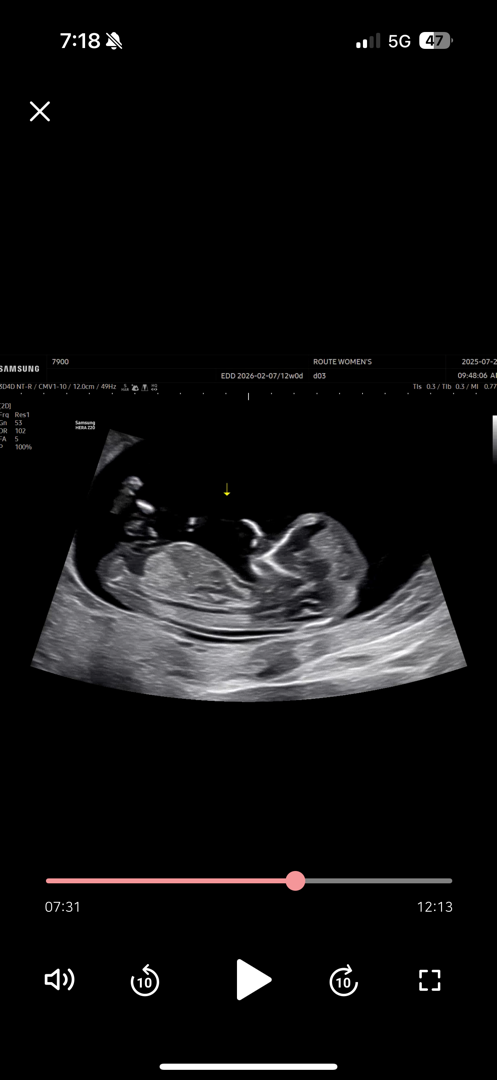

12주 각도법! 성별 궁금해용

아들일까요 딸일까여?! 뭐든 상관없지만 궁금해요 ㅠㅜ

흐러서 잘 안보이는데 제가 보는 부분이 생식기가맞다면 각도로는 아들같아요!